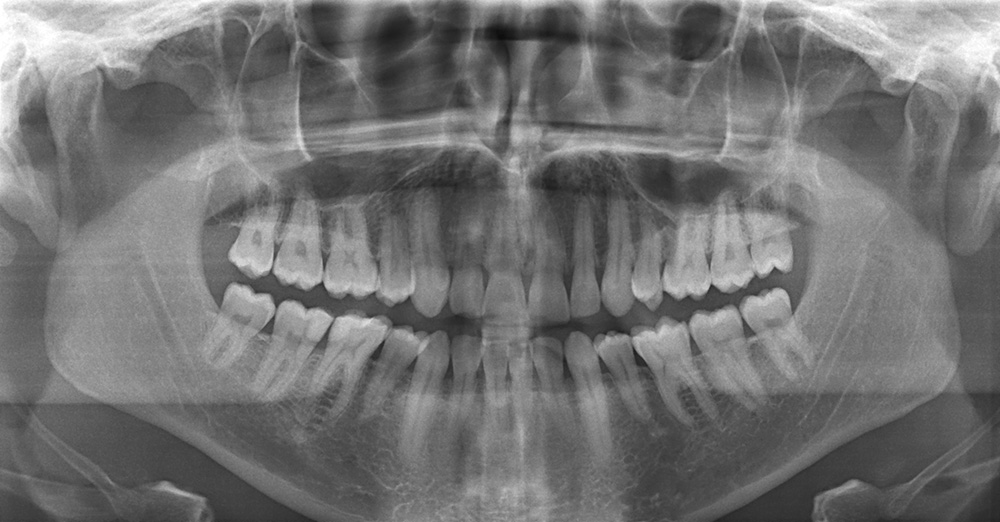

Le panoramique dentaire est une radiographie qui permet de visualiser sur un seul cliché (une seule radio), entre autres :

- Les arcades dentaires.

- Les maxillaires.

- Les parties inférieures des fosses nasales.

- Les sinus maxillaires.

Chez l'enfant, le panoramique dentaire permet de visualiser l'ensemble des germes des dents définitives, c'est-à-dire des futures dents de l'adulte. Ceci autorise l'évaluation de l'âge dentaire.

Cette incidence radiologique, diagnostique également, les lésions situées aux extrémités des racines des dents comme par exemple un granulum.

Radiographie panoramique dentaire